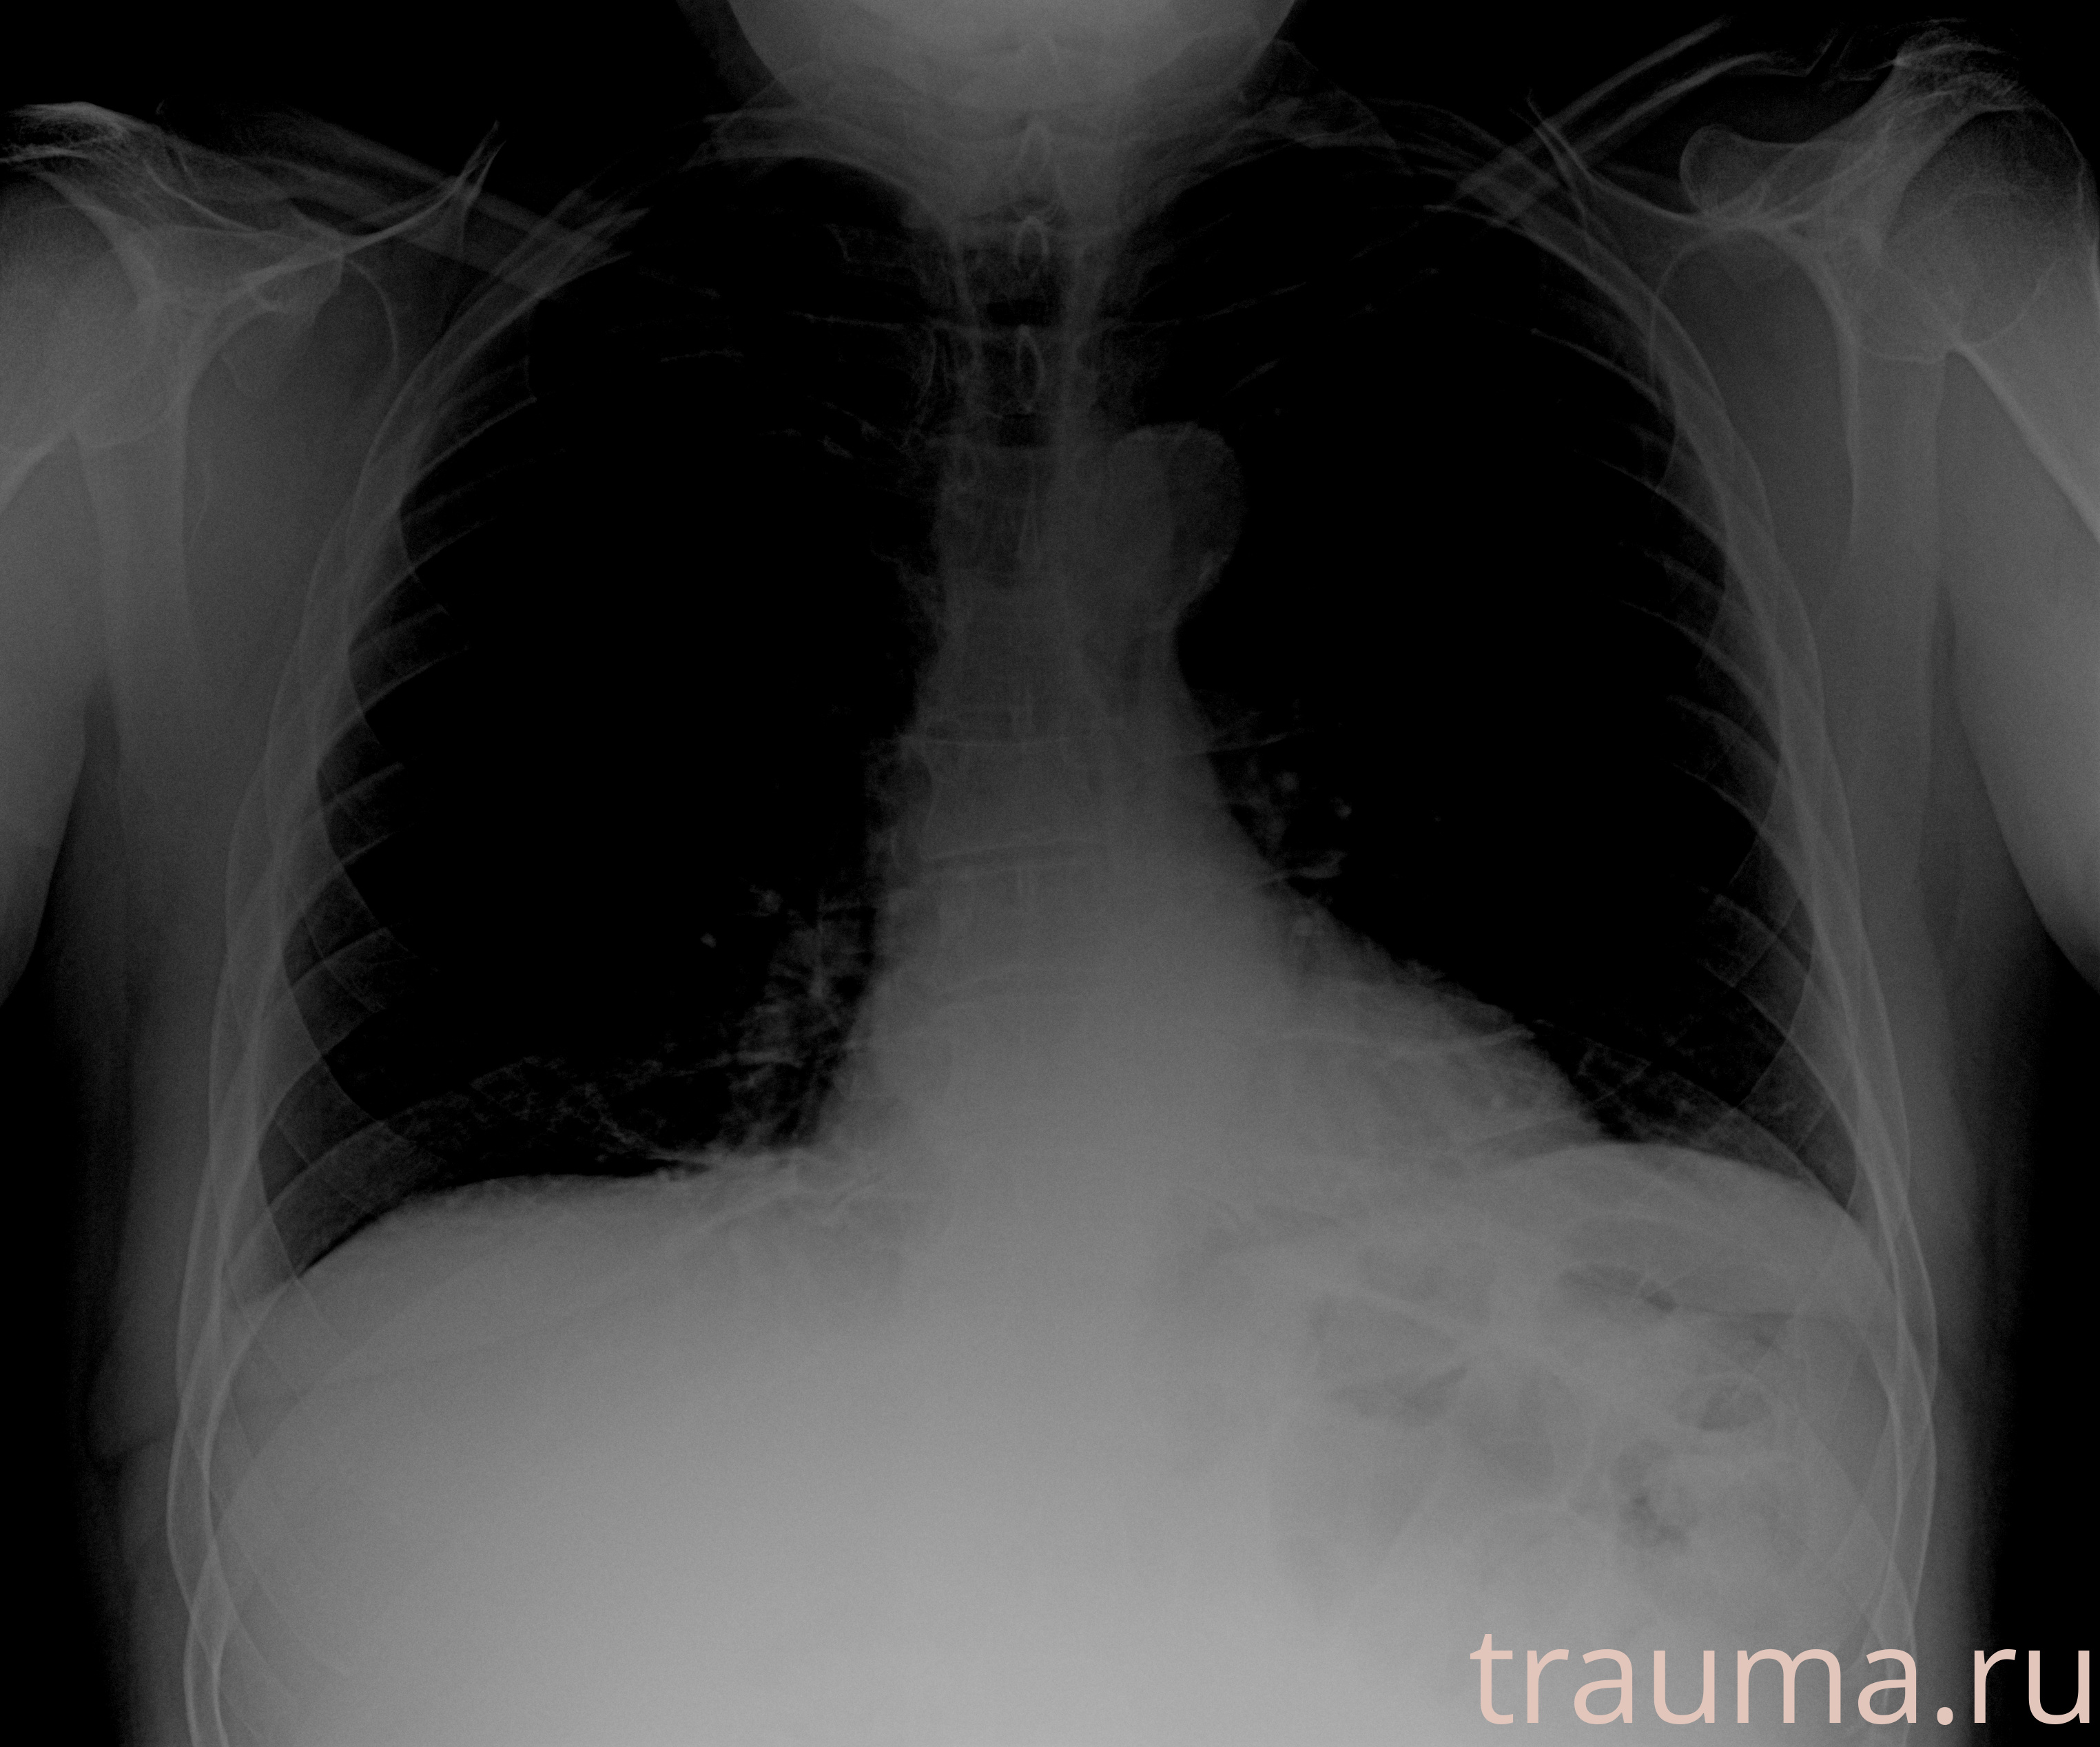

Рентген на дому: по вашему адресу приезжает врач-рентгенолог, травматолог-ортопед с мобильным рентгеновским аппаратом, проводит диагностику травмы или заболевания, делает необходимые рентгенограммы, дает рекомендации по дальнейшему лечению. Получить качественные снимки в домашних условиях возможно благодаря уникальной методике, разработанной МосРентген Центром для института  Склифосовского